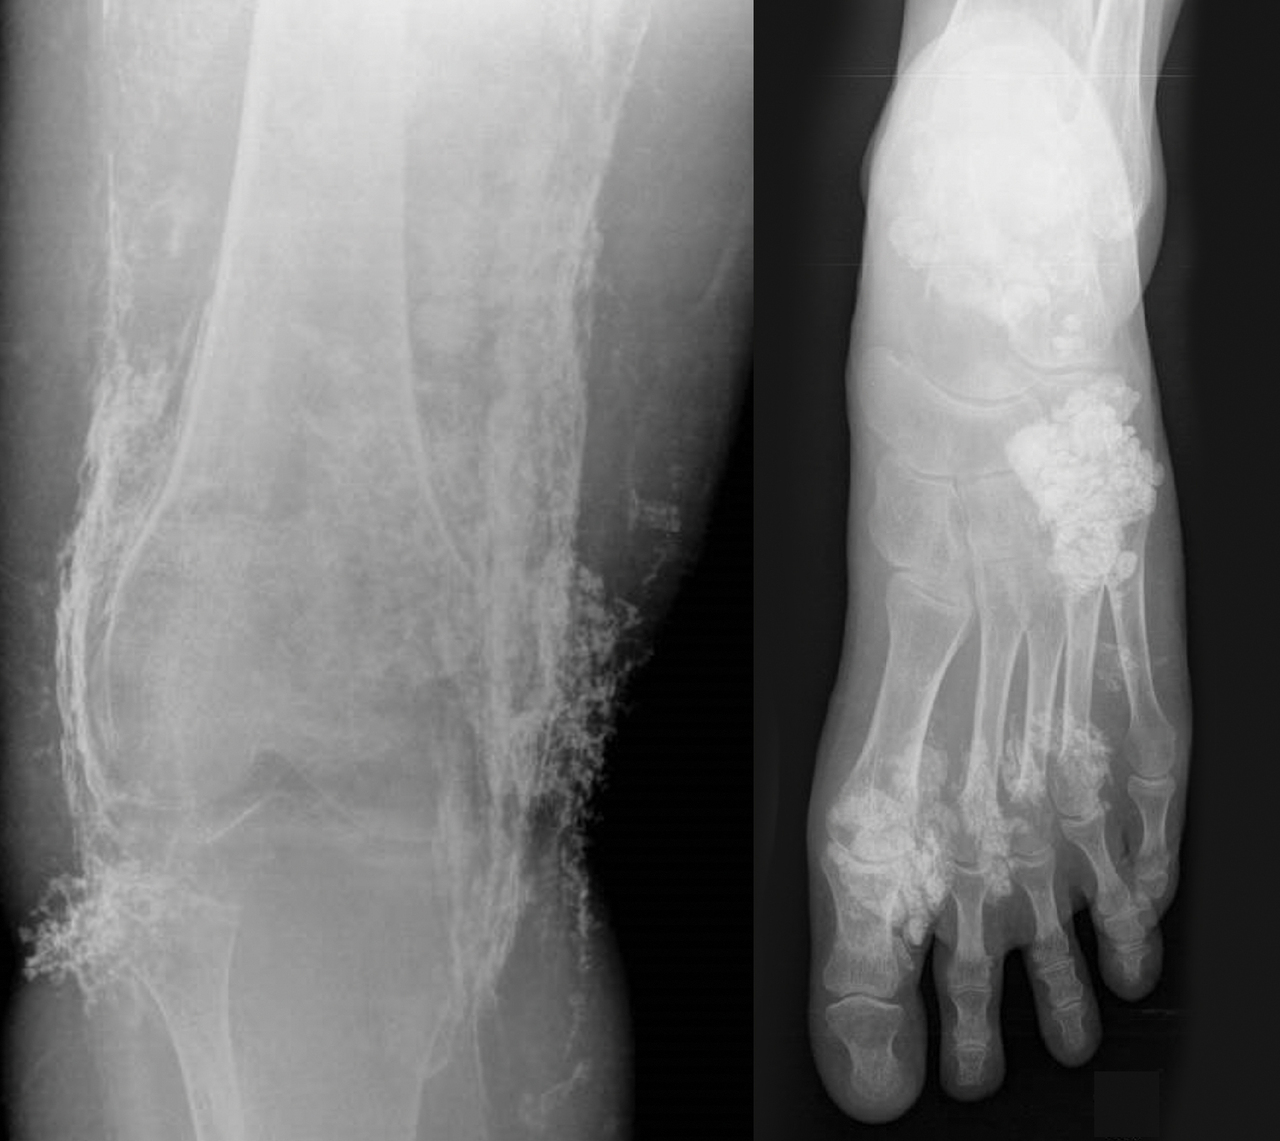

Une femme de 34 ans décrit des arthralgies, des myalgies et un déficit moteur proximal.

Quel est votre diagnostic ?